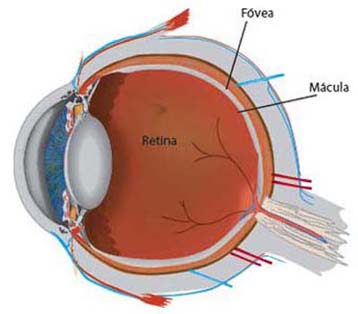

La Retina consta de dos partes: la retina periférica y la mácula. Si imaginamos la retina como un círculo con una diana en el centro, la mácula es la diana, muy pequeña pero es la responsable del 90% de nuestra capacidad de discriminación. La zona amplia de retina que rodea la mácula y que constituye el 95% de la misma, se denomina retina periférica. Nos proporciona visión lateral, denominada visión "periférica", es la parte de la retina que actúa cuando vemos alguna cosa situada por fuera del punto de enfoque central.

Puesto que la retina periférica no es capaz de ver los detalles con claridad, no la podemos usar para leer, enhebrar una aguja, conducir ni reconocer una cara. Si vemos a alguien situado hacia nuestro lado, podemos decir de quién se trata porque reconocemos la silueta general de la persona, pero no podemos ver la expresión de su cara.

Diagrama

Retinografía